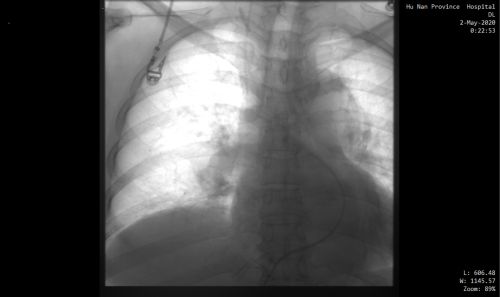

下腔静脉滤器植入前。

下腔静脉滤器植入后。